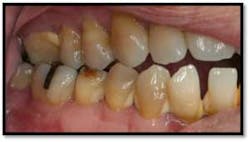

Tissue is light pink, tight and firm. All pockets are 1-3mm, no BOP

LR lingual post Tx and LL lingual post

Tissue is light pink, tight and firm. Pockets 1-3mm no BOP

Charting shows that all pockets are now generalized 1-3 mm with no BOP